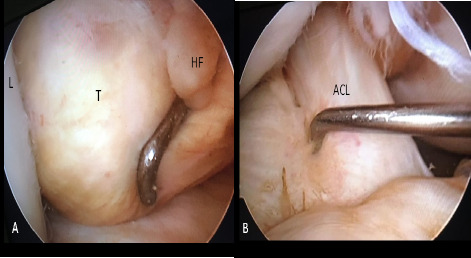

Tenosynovial giant cell tumor (GCT) is a rare, benign disorder involving the joint's synovial lining, tendon sheath or bursa. It can be classified as localized or diffuse based on its pattern and behavior. Localized form is extremely rare in knee joint. We present an unusual case of localized form of GCT in Hoffa's fat pad in a young female, treated with arthroscopic resection and monitored for over two years with no recurrence. Despite its rarity, GCT of Hoffa's fat pad should be considered in cases of non-traumatic knee pain.